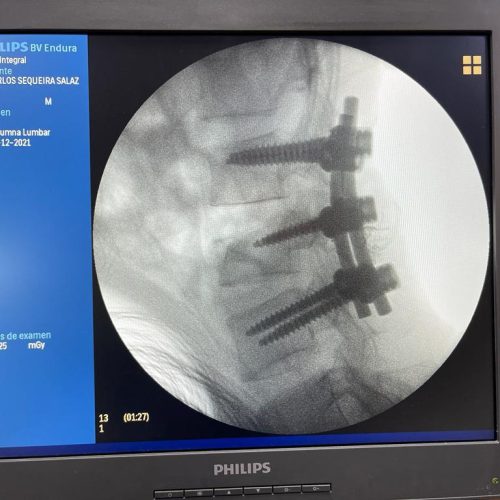

4. Fusión Vertebral (Lumbosacra o Cervical)

¿Qué es?

Cirugía que une dos o más vértebras para estabilizar la columna y aliviar el dolor.

Fusión Vertebral (Cervical o Lumbosacra)

Es un procedimiento quirúrgico que busca estabilizar la columna vertebral uniendo de forma permanente dos o más vértebras. Se utilizan tornillos, barras y, en ocasiones, una caja intersomática con injerto óseo, para que las vértebras se fusionen en una sola unidad sólida.